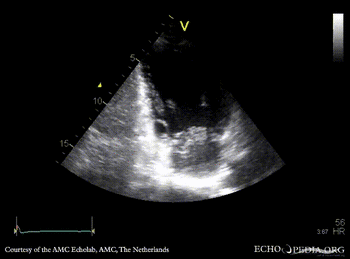

| PLAX: thickend mitral valve leaflets, prolaps of PMVL